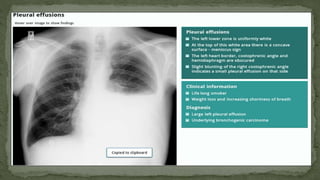

Pleural effussion left

Pleural effussion right